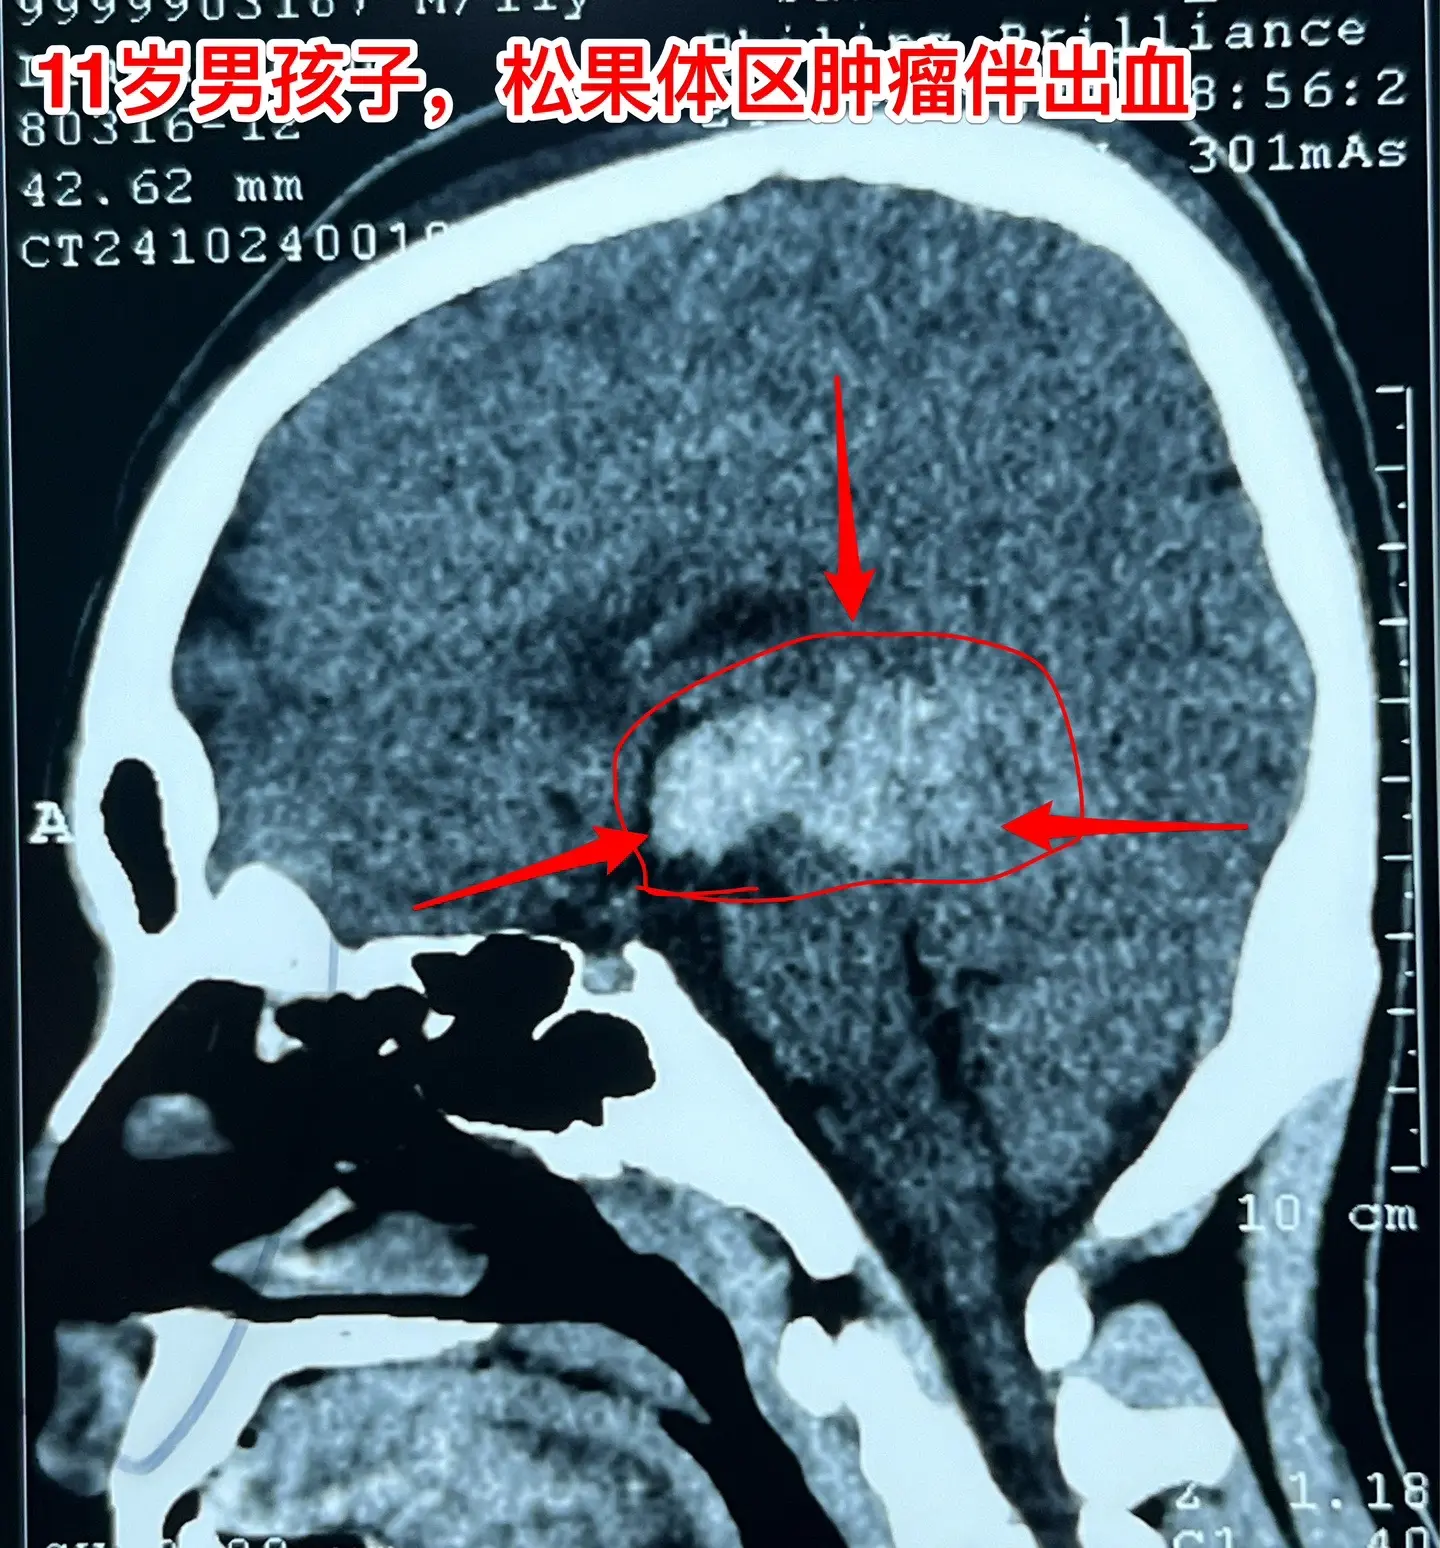

松果体区的绒毛膜癌(绒癌)很罕见。通常情况下,绝大多数的绒癌与女性怀孕过程的滋养细胞有关系,可以造成子宫内出血。 但是,脑部有一种恶性肿瘤称为绒癌,是生殖细胞肿瘤中的一种,很罕见,一般见于鞍区和松果体区。 这个11岁济宁市的男孩子于2024年10月底18日突发头痛、恶心、呕吐,在当地医院行头部CT检查发现了脑部有出血,出血的位置位于松果体区及第三脑室里,和普通的脑出血位置不一样。经过急诊手术(脑室外引流术)后保住了生命。磁共振检查显示松果体区有个肿瘤,考虑是肿瘤卒中出血了。转到我院化验HCG,达到正常值的600多倍。 2024年10月27日在我科作了手术,将肿瘤切除了,手术后小男孩身体恢复顺利,HCG逐步下降到正常范围。病理报告是纯绒癌! 这个脑部的绒癌是生殖细胞肿瘤中的一种,恶性度高,手术后需要作化疗+放疗。